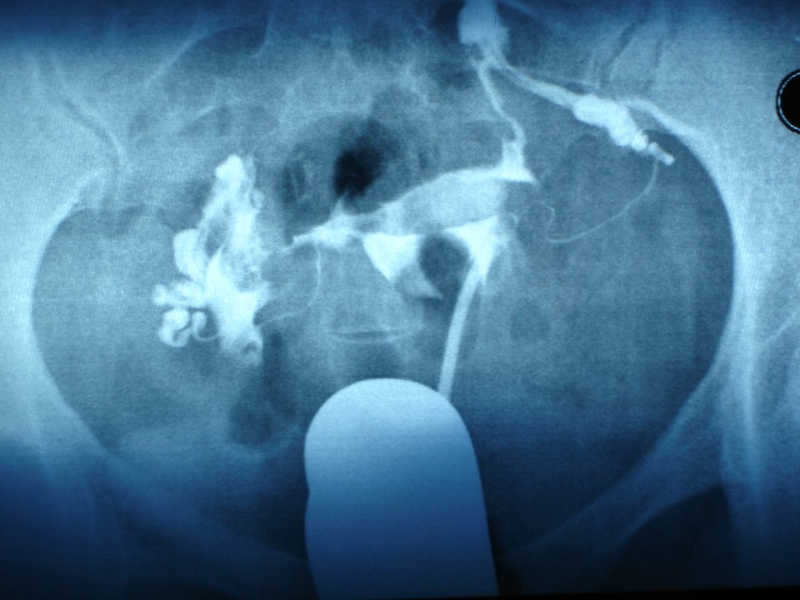

首先,产科大夫会把手从产道中伸进去,伸到子宫中,几乎半只胳膊就进去了,摸到胎盘附着的位置。

然后,产科大夫会用另一只手压住妈妈的肚子,扶好不让胎盘的位置乱动,然后用手指沿着胎盘和子宫附着的位置一点点抠出来。如果顺利的话,整个胎盘能全部取出。

把大块胎盘取出后,接下来,手还要伸进子宫,再去摸一遍,检查子宫壁上是否有胎盘的碎片残留,因为必须要清理的干干净净。

最后,产科大夫就要讲妈妈的肚子压住,让子宫恢复到正常。